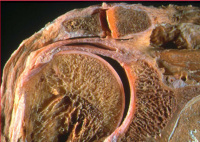

Abbildung 4: Frakturprothese, Tubercula nicht eingeheilt

Mineralstoffwechsel

Prothese

Röntgenbild

Schultergelenk